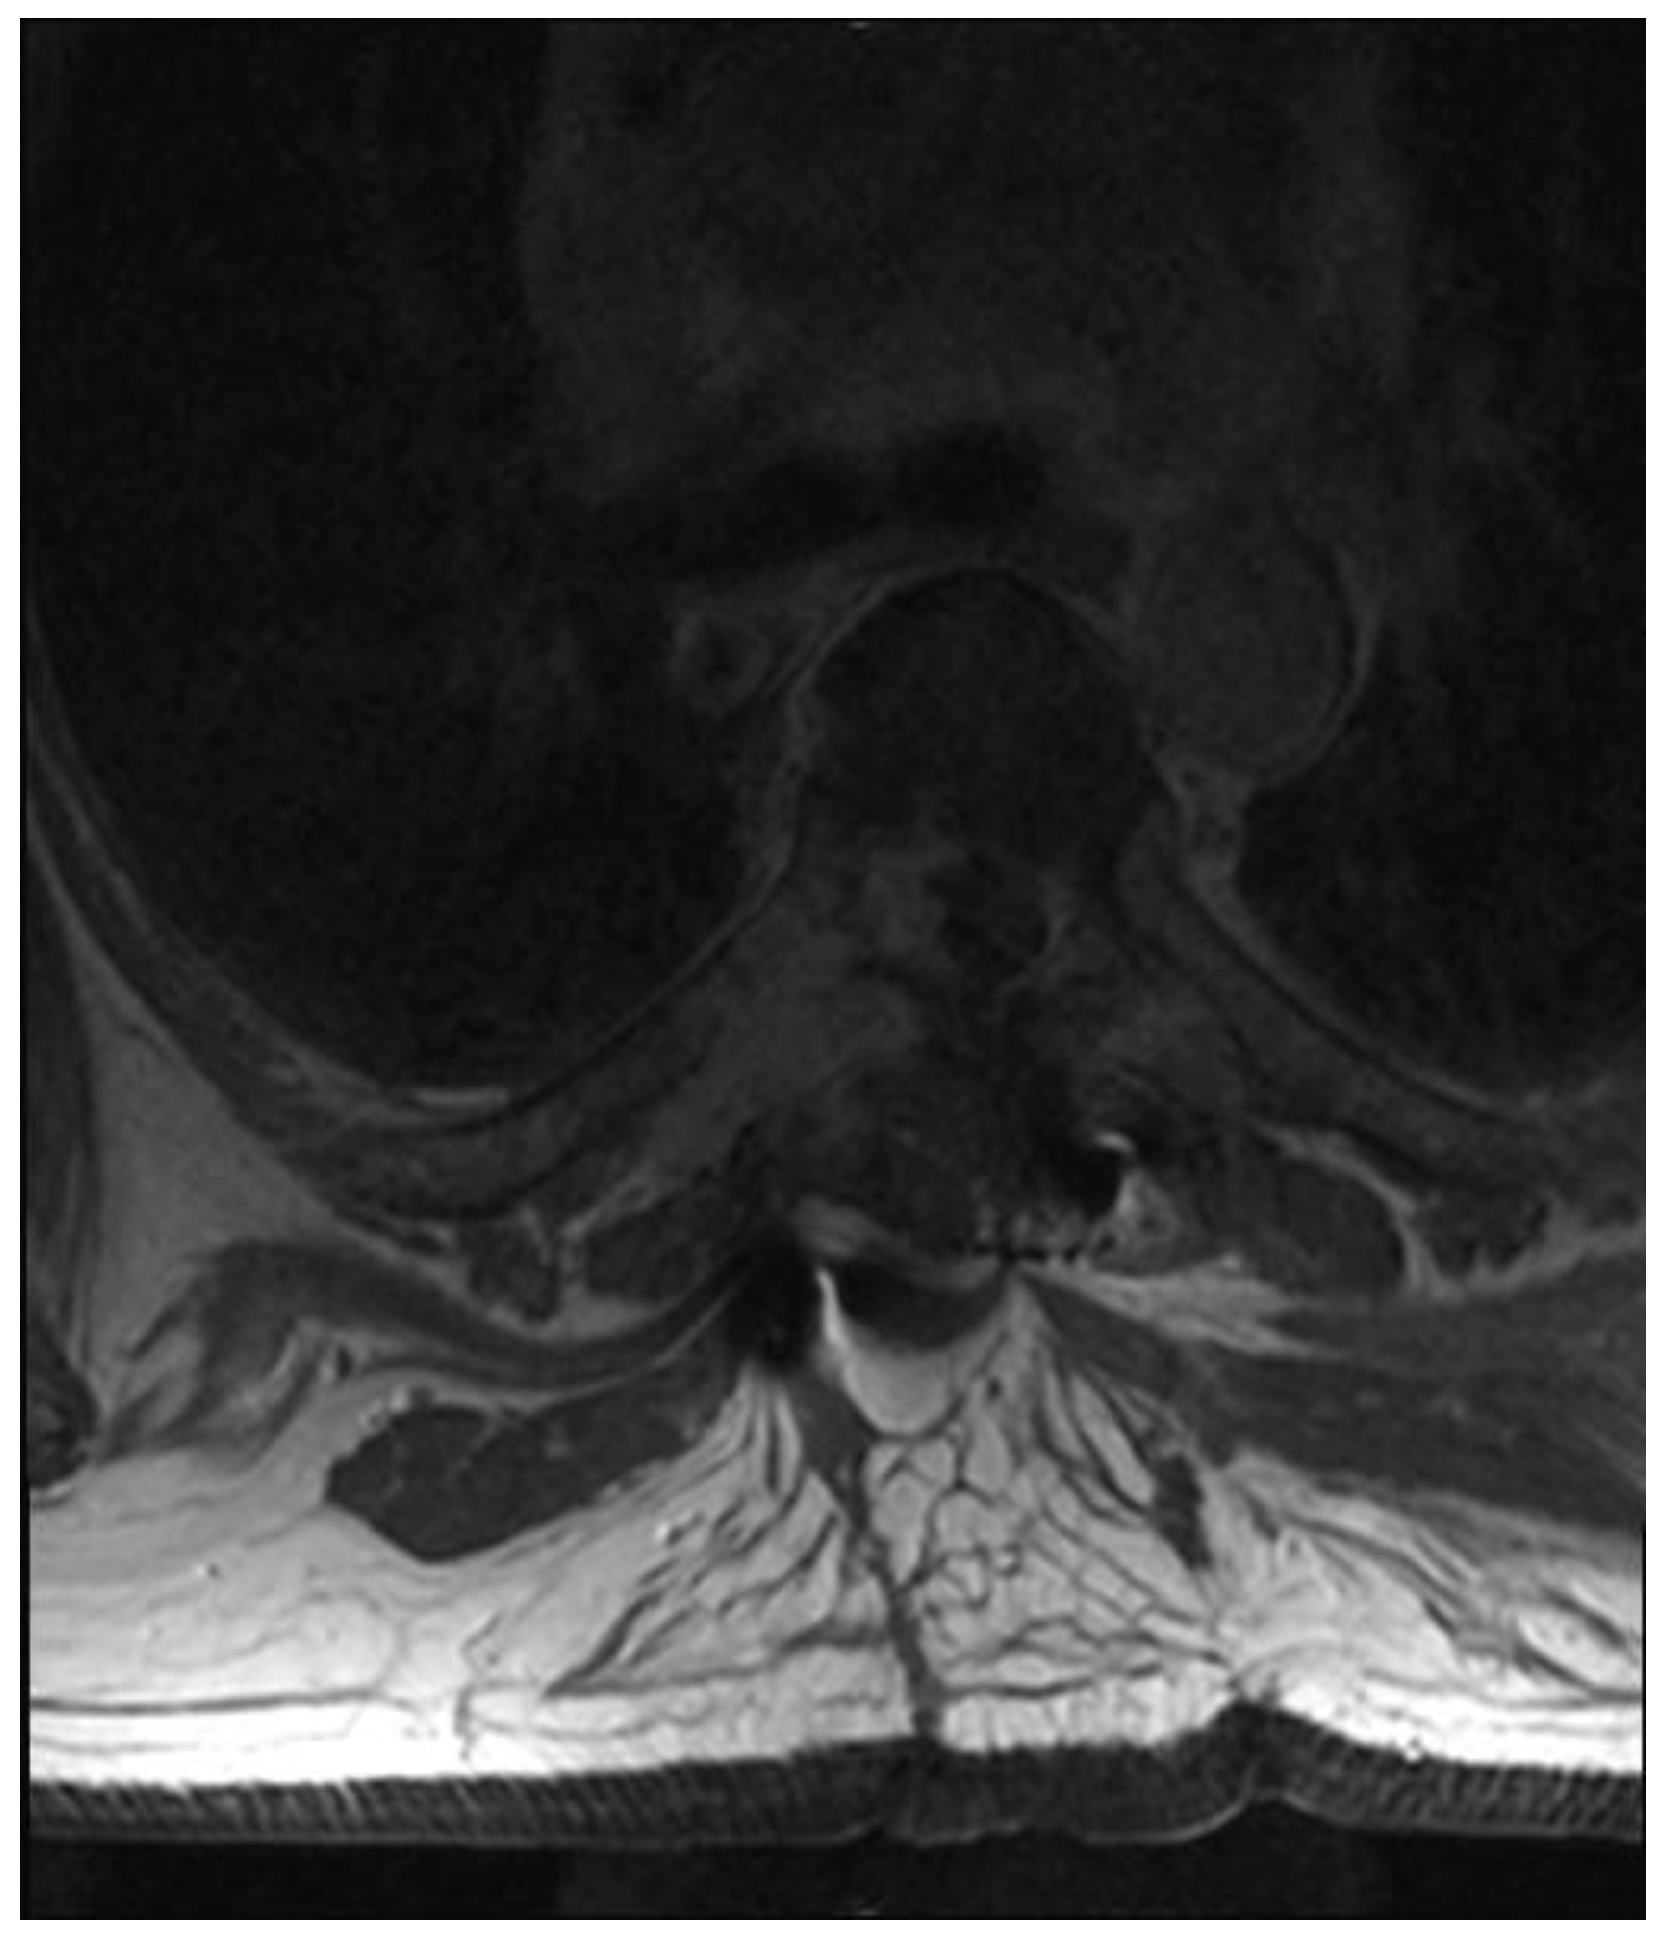

Fully Endoscopic Spine Separation Surgery in Metastatic Disease—Case Series, Technical Notes, and Preliminary Findings

3. Results